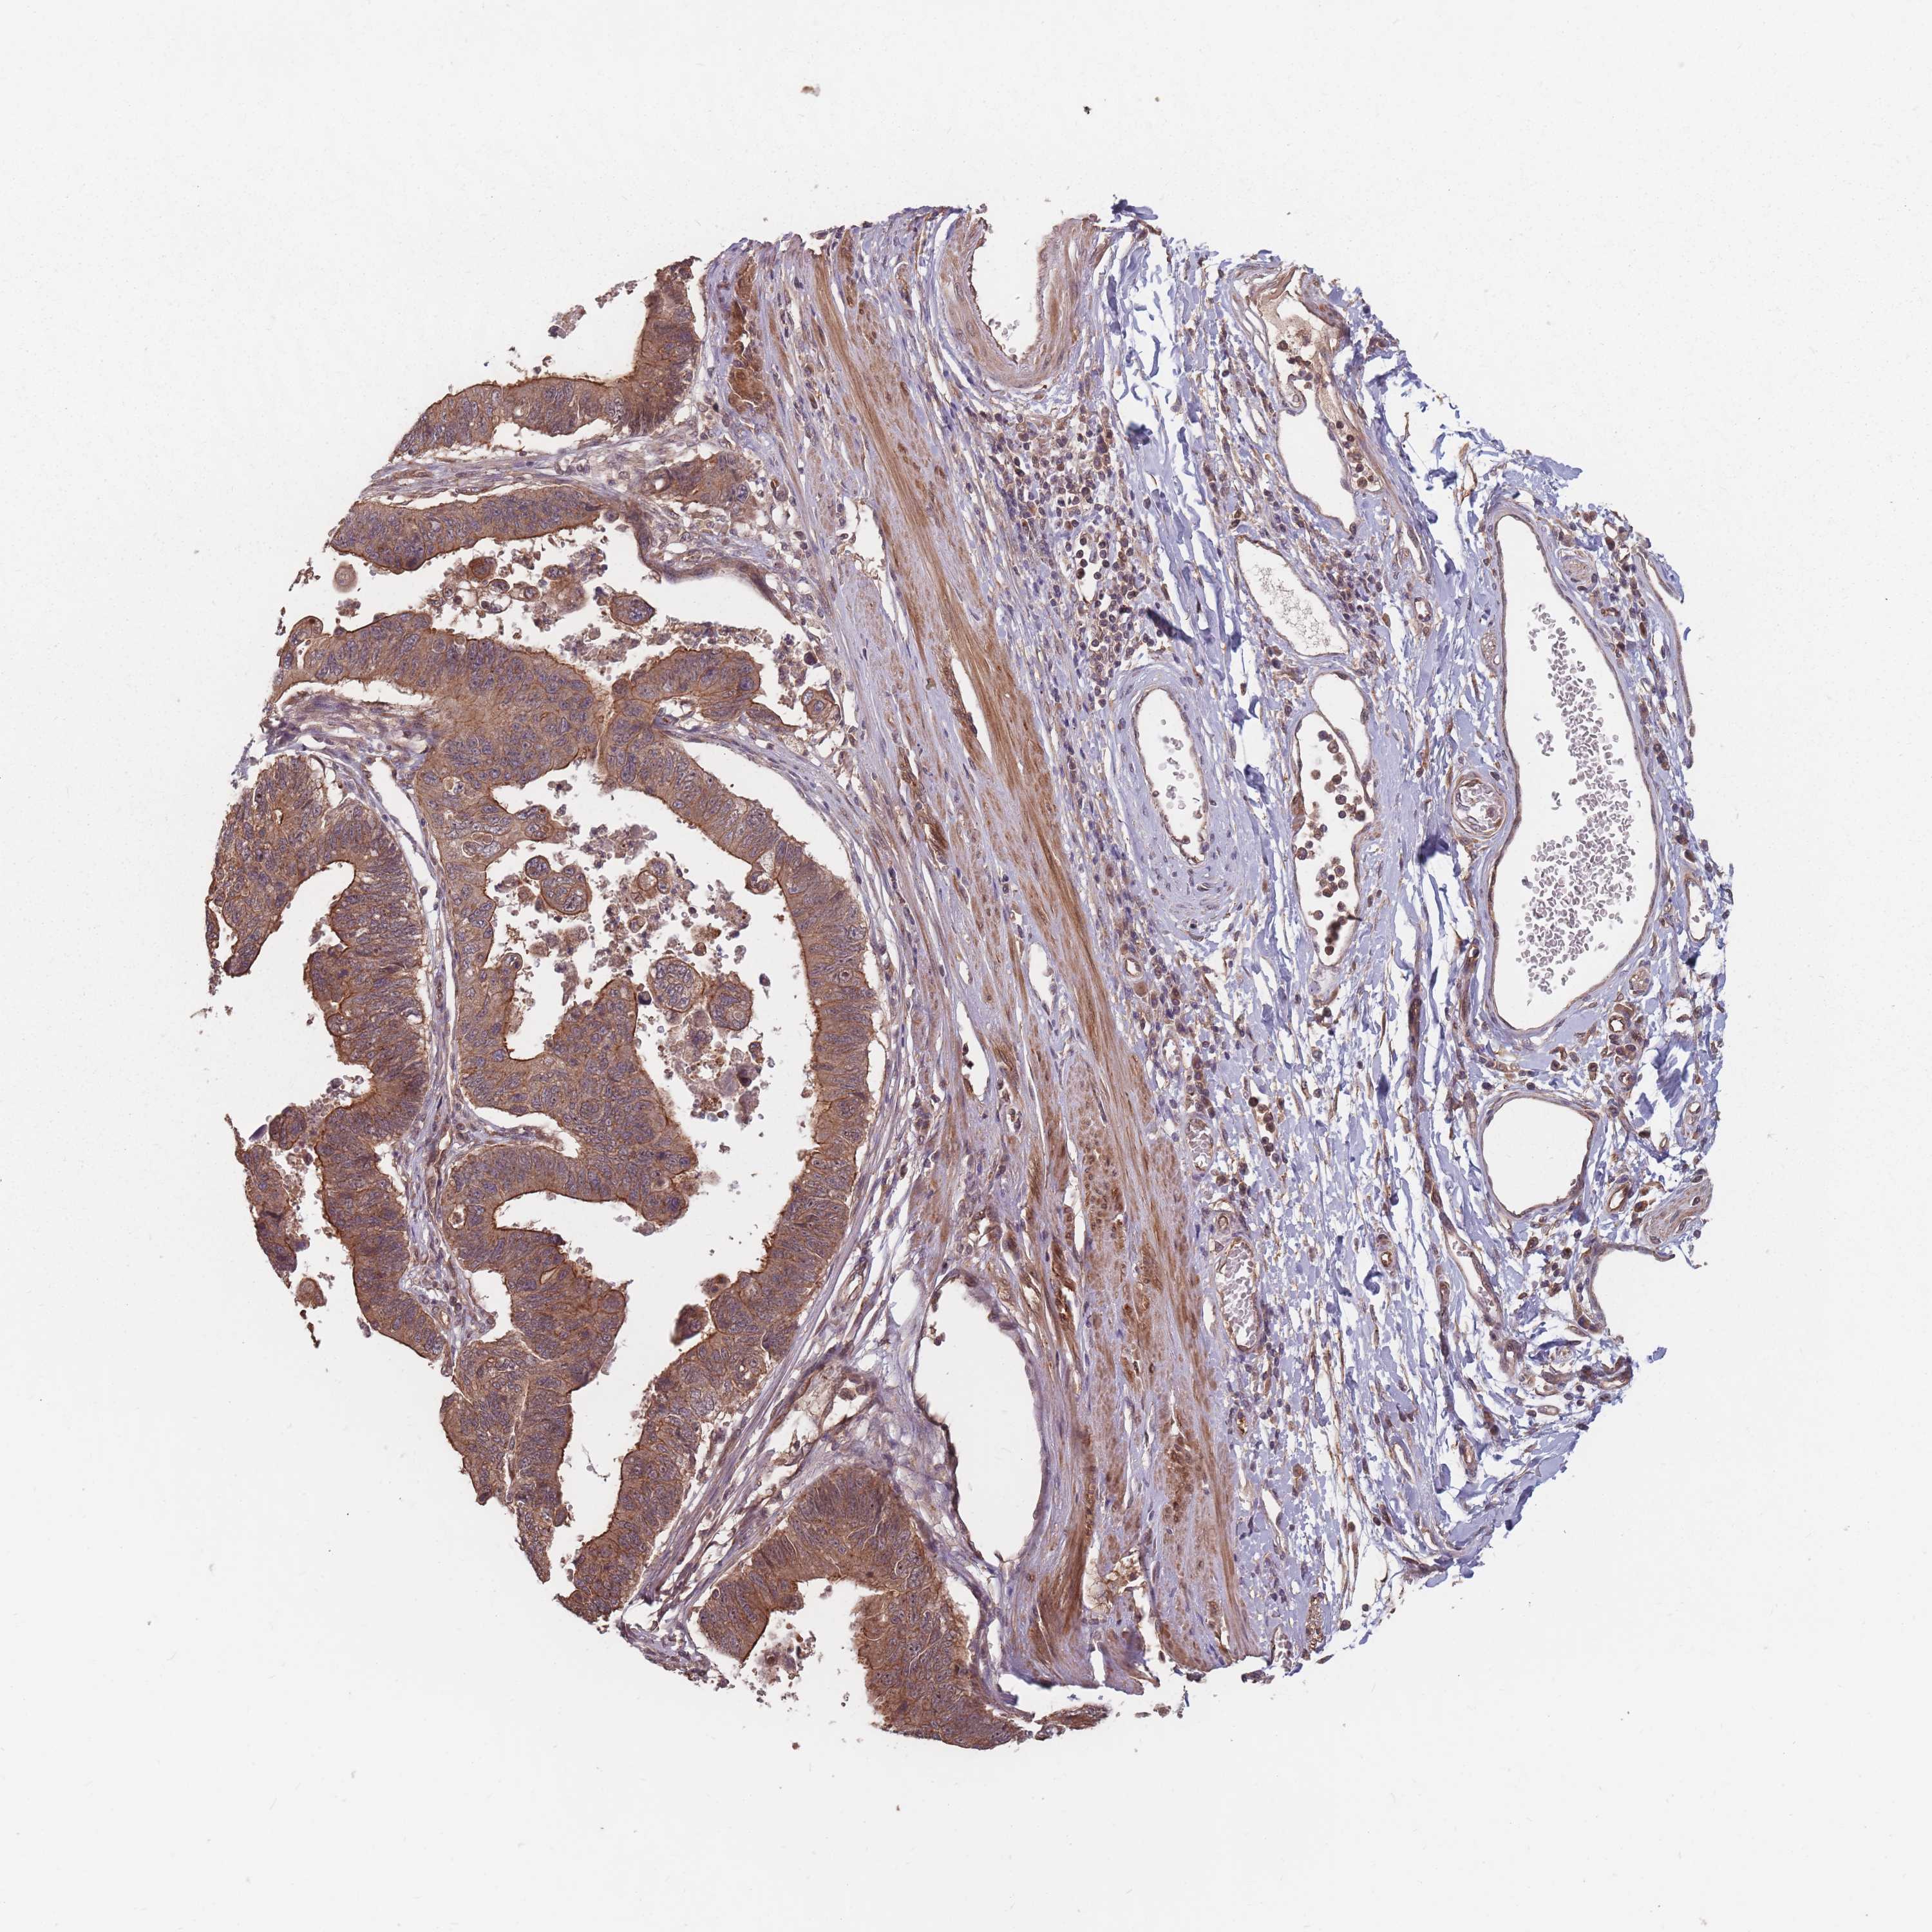

STOMACH CANCER - Protein expressioni

A mouse-over function shows sample information and annotation data. Click on an image to view it in a full screen mode. Samples can be filtered based on level of antibody staining by selecting one or several of the following categories: high, medium, low and not detected. The assay and annotation is described here.

Note that samples used for immunohistochemistry by the Human Protein Atlas do not correspond to samples in the TCGA dataset.

Antibody stainingi

Antibody staining in the annotated cell types in the current human tissue is reported as not detected, low, medium, or high, based on conventional immunohistochemistry profiling in selected tissues. This score is based on the combination of the staining intensity and fraction of stained cells.

Each image is clickable and will lead to virtual microscopy that enables deeper exploration of all samples and also displays staining intensity scores, fraction scores and subcellular localization as well as patient and tissue information for each sample.

Antibody HPA048286

Staining

High

Medium

Low

Not detected

Intensity

Strong

Moderate

Weak

Negative

Quantity

>75%

75%-25%

<25%

None

Location

Nuclear

Cytoplasmic/membranous

Cytoplasmic/membranous,nuclear

Adenocarcinoma, NOS